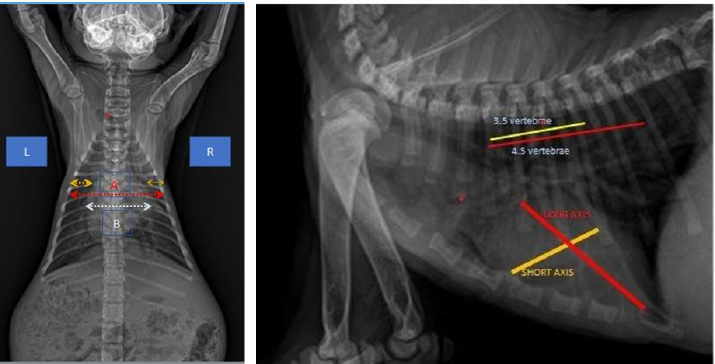

In examining the size of the heart via dorsoventral X-ray, the method used is a comparison of the width of the heart and the width between the right and left ribs and the comparison of the length of the boundaries of the right and left ribs with the heart. The measurement results in (Fig. 6) show a comparison of the length of the border of the right and left ribs with the heart RL, the length of the border between the ribs and the heart on the dexter and sinister parts is not the same (abnormal). In measuring the comparison of the width of the heart and the width between the right and left ribs, length B is greater than 2/3 A (abnormal), whereas normal is BA (Holland, 2020).

When evaluating the cardiac dimensions through dorsoventral X-ray analysis (Birsan et al., 2017), a technique employed involves assessing the heart’s width relative to the space between the right and left ribs, as well as comparing the length of the right and left rib margins concerning the heart. The findings in Figure 6 indicate a comparison between the length of the border of the right and left ribs against the heart RL. Notably, there exists an abnormality in the length of the border between the ribs and the heart on the dexter and sinister parts, as they are not of equal dimensions. According to Holland (2020) findings, aberrant results were obtained when assessing the ratio of the width of the heart to the width between the right and left ribs, with length B being greater than 2/3 A. In contrast, a normal outcome was observed when the ratio of B to A was within typical parameters.

The way to measure the heart with the vertebrae heart size (VHS) method is by measuring it by drawing straight lines on the short axis and long axis (James, 2000), then the measurement results are aligned with the vertebrae and starting from the 4th rib (Marbella et al., 2023) then add up by looking at how long the vertebrae are. The normal size of VHS in the Buchanan and Bucheler method is 7.5 vertebrae (VT). In the case of Hiro’s cat (Fig. 6). VHS size using the Buchanan and Bucheler method (Litster and Buchanan, 2000) is 8 vertebrae with a long axis of 4.5 VT and a short axis of 3.5 VT so that the total becomes 8 VT (larger than normal size).

Fig. 6. Method of measuring the heart in the DV position (Left). Heart measurement with the VHS method of the Buchanan and Bucheler methods (Right).

During the X-ray examination, heart measurements were taken to identify any changes in the size of the heart organ. The lateral view measurements resulted in an intercostal measurement technique score of 4, with a normal range of 2.3–3.5. The height from the apex to the vertebral column was also measured compared to the carina, resulting in A being greater than 1/3 A + B and B being greater than 2/3 A + B (normal values are A < 1/3 A + B and B < 2/3 A + B). The VHS was also measured, and there was an increase in VHS results in CHF cases as mentioned in previous research in cats (Smith et al., 2004; antecedent corticosteroid administration has been noted in cats with congestive heart failure (CHFLaudhittirut et al., 2020), resulting in a score of 8 VT (the normal value is 7.5 VT). Measurements were then taken using the dorsoventral position, resulting in the heart size being different in R and L distances, with L being larger than R. The size of B was also greater than 2/3 (normally, R is equal to L, and B is less than 2/3). From these measurements, it was determined that the heart was enlarged or experiencing cardiomegaly. Cardiomegaly is the heart’s compensation for heart failure to meet the body’s circulatory needs, which can be caused by congestive heart failure (CHF), valvular heart disease, and cardiomyopathy (Triakoso, 2020).